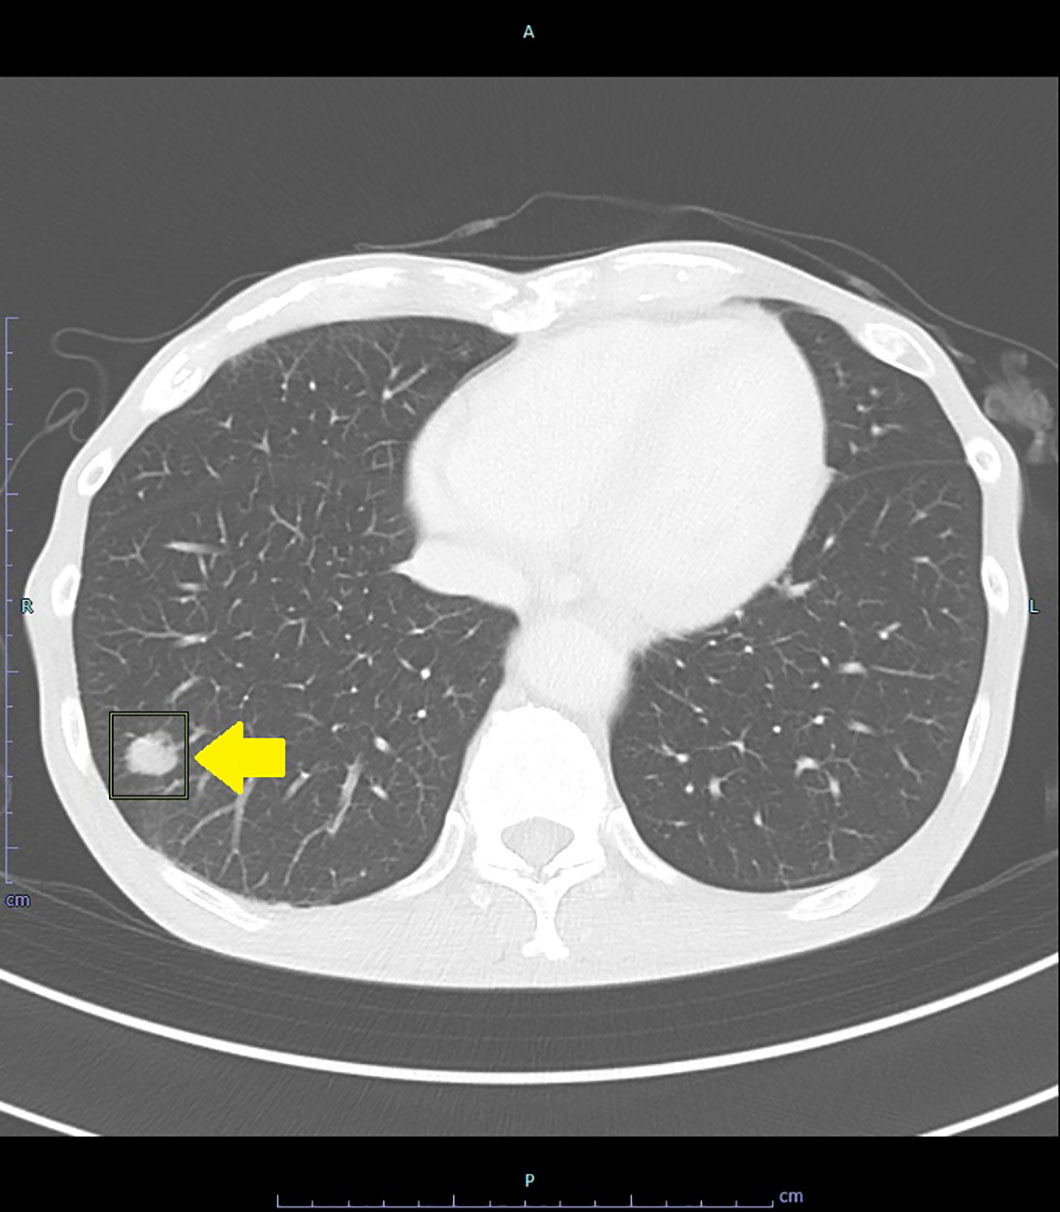

直腸癌の肺転移

症状

特になし